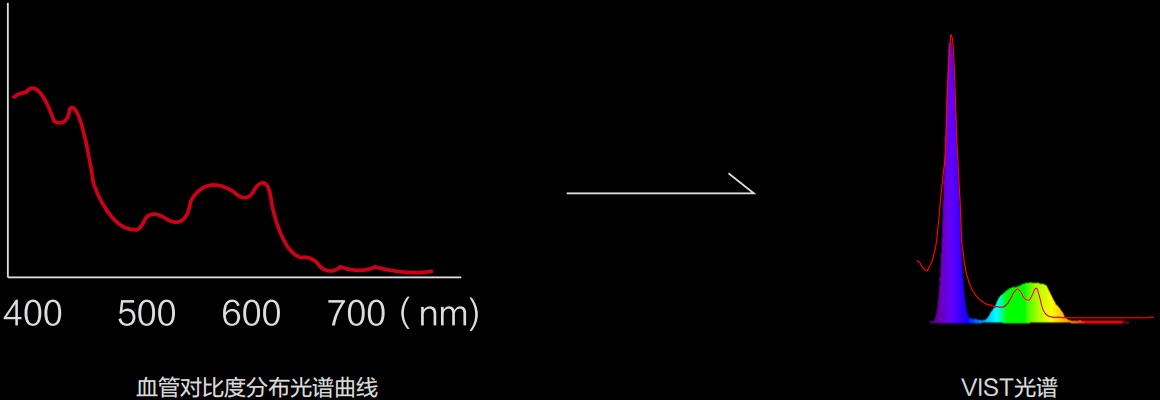

(Versatile Intelligent Staining Technology)

利用了血红蛋白在不同波长吸收下系数不同的原理,设计的一种光学域滤波和数字域滤波结合的染色技术,既保证了图像亮度,又可增强黏膜血管的对比度,充分凸显早期病变的细微结构变化,为临床疾病的观察诊断提供更丰富的参考信息。

• 蓝紫光 LED 中心波长位于血红蛋白最大吸收峰,凸显血管对比度,有助病灶识别和诊断